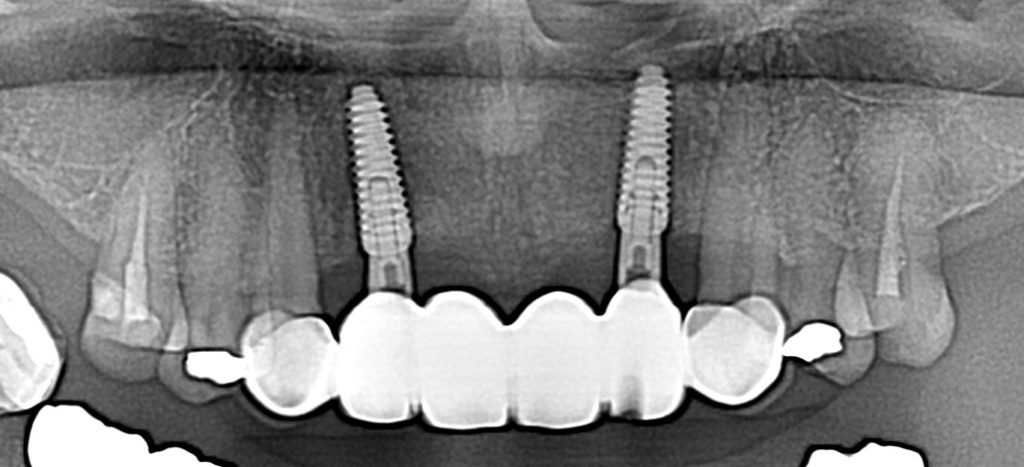

症例240代 女性 主訴 義歯が動いて煩わしい

治療前

治療後

入れ歯だと奥歯しっかり噛めず、取り外しも煩わしいので固定制のインプラントにして欲しいと訴え来院。

左右大臼歯部は、残存骨が1~2㎜程度で骨高が不足している為、ソケットリフト(上顎洞洞底膜挙上術)を行い、インプラントを埋入。口腔内全体で7本のインプラントを埋入。

約4ヶ月の治療期間を経て、全てジルコニアを装着し終了。

リスクとしては外科的侵襲がある。デメリットは、保険外診療の為、経済的負担がある。

費用 381万(税込)(オペ・仮歯・最終補綴物まで含む)